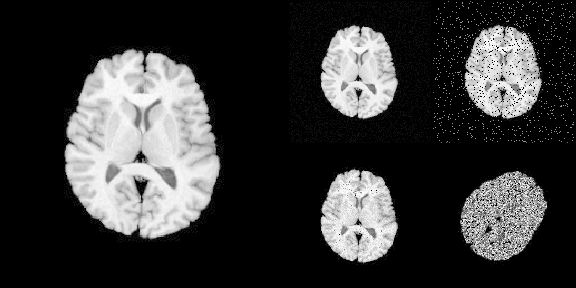

To load imaging data into R

# Use [] to convert ANTsImage into R array

is.array(img[])

#> [1] TRUE

# plot via R

layout(matrix(c(1,1,2,3,1,1,4,5), nrow = 2, byrow = TRUE))

par(mar = c(0.1, 0.1, 0.1, 0.1), bg = "black", fg = "white")

pal <- grDevices::gray.colors(256, start = 0, end = 1)

image(img[], asp = 1, axes = FALSE,

col = pal, zlim = c(0, 255), ylim = c(1, 0))

image(noise_image1[], asp = 1, axes = FALSE,

image(noise_image2[], asp = 1, axes = FALSE,

image(noise_image3[], asp = 1, axes = FALSE,

image(noise_image4[], asp = 1, axes = FALSE,